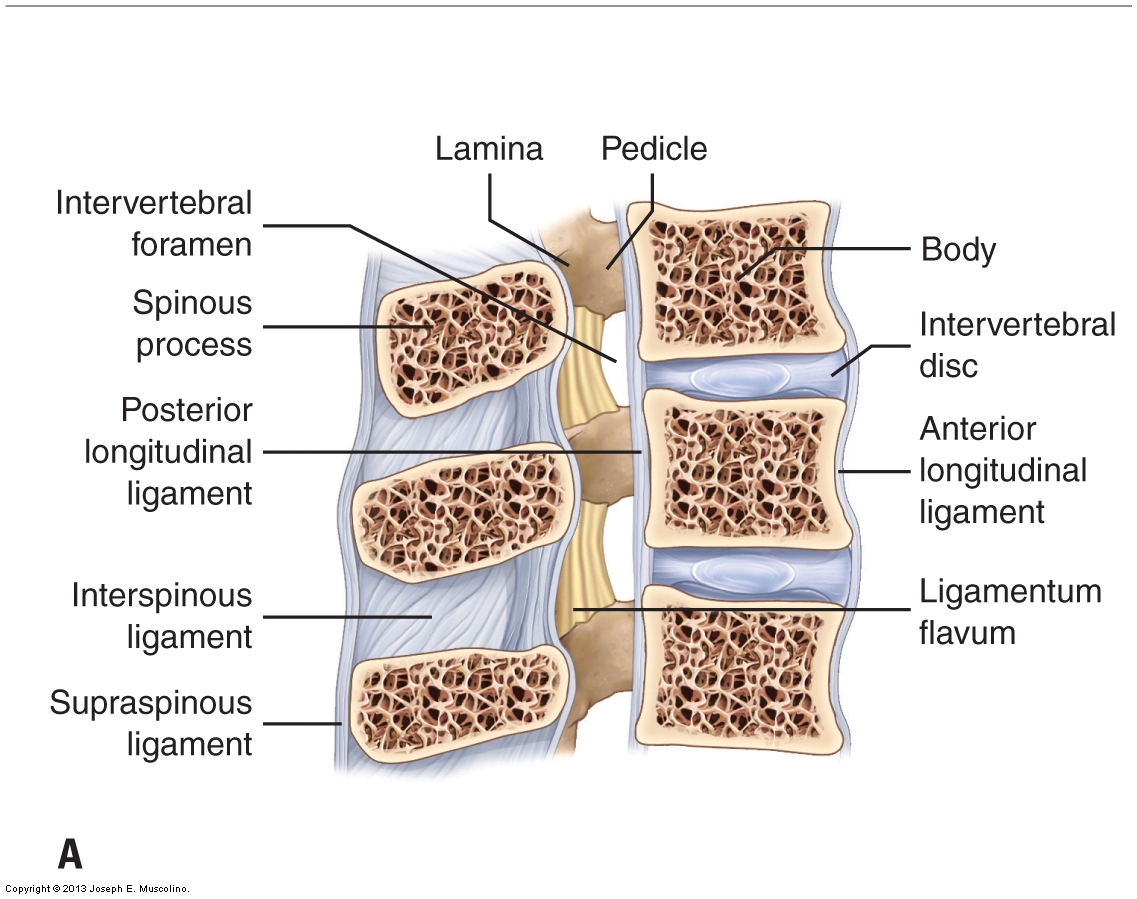

Pure Health - Anatomy 101 - Supraspinous ligament and interspinous ligament 📚 The supraspinous ligament and interspinous ligament work together to limit flexion of the spine by limiting separation of the spinous

DOCS - The interspinous ligament is located between the spinous processes of adjacent vertebrae in the spine. It extends from the base of one spinous process to the apex of the next,

Notes on Anatomy and Physiology: The Spinal Ligaments – Holding All The Parts Together |